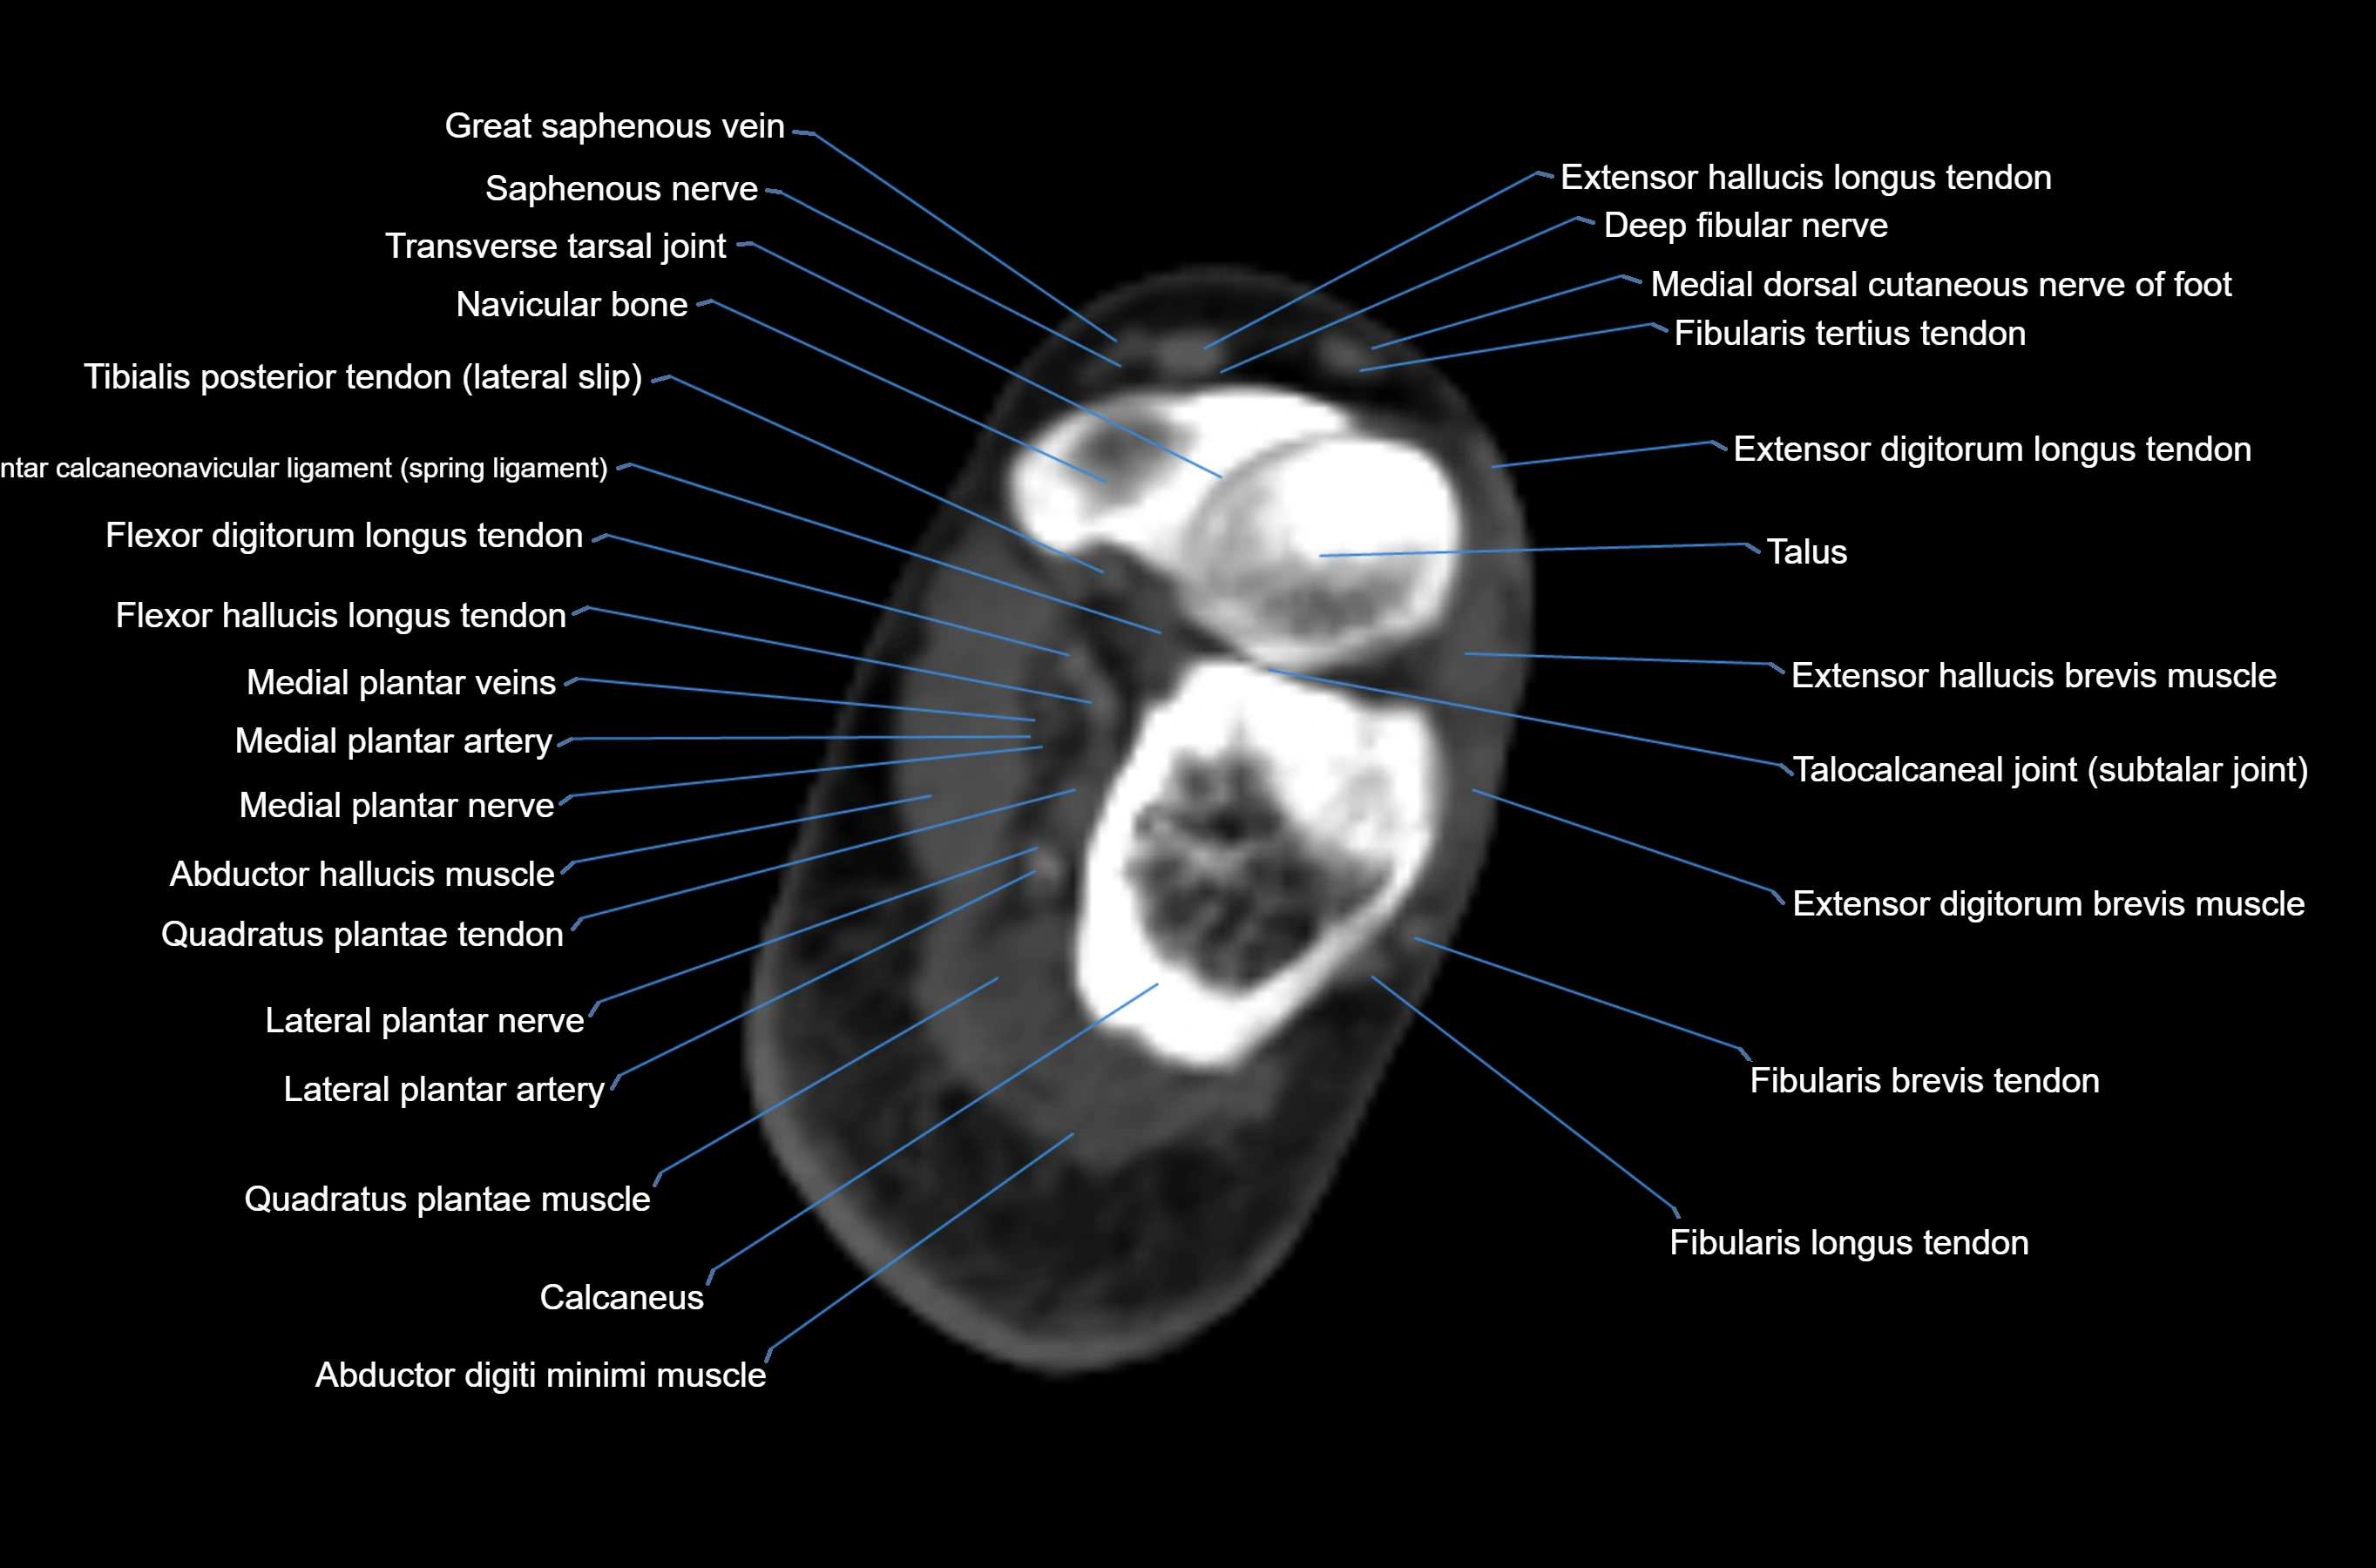

CT image